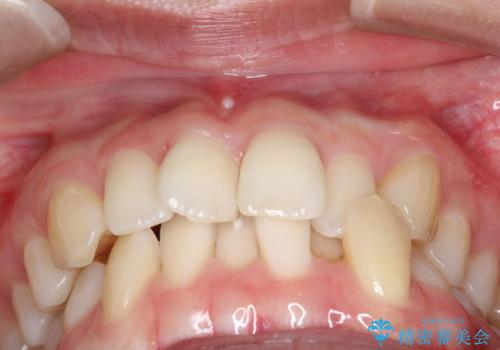

【インビザライン】 前歯の反対咬合を治したい

左下5番は先天性欠損のため乳歯は抜歯しインプラントにて欠損補綴しています。